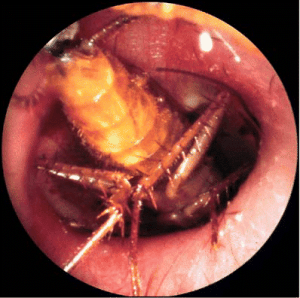

Sieros kamštis dažniausiai šalinamas jį išplaunant, atsiurbiant siurbliu. Jei nepavyksta jo pašalinti, skiriami sieros kamštį minkštinantys riebaliniai lašai (Tropex, Cerustop, Waxol). SvetimkūnisSvetimkūnis išorinėje klausomojoje landoje dažniau aptinkamas vaikams, taip pat patyrus traumas ar pabuvus miške.

Klinika. Ligoniai, kurių išorinėje klausomojoje landoje yra svetimkūnis, gali skųstis skausmu, ypač jei svetimkūnis aštriomis briaunomis, klausos pablogėjimu, ausies užgulimu.

Gydymas. Daugelį svetimkūnių galima pašalinti juos išimant žnyplutėmis arba išplaunant, tačiau įstrigusį svetimkūnį, taip pat tais atvejais, kai vaikas nesiduoda apžiūrimas, indikuotina intraveninė nejautra. Jei svetimkūnis – vabalas ar vabzdys, pirmiausia reikėtų jį numarinti į ausį sulašinus riebalų, vėliau išplauti ar ištraukti žnyplutėmis.